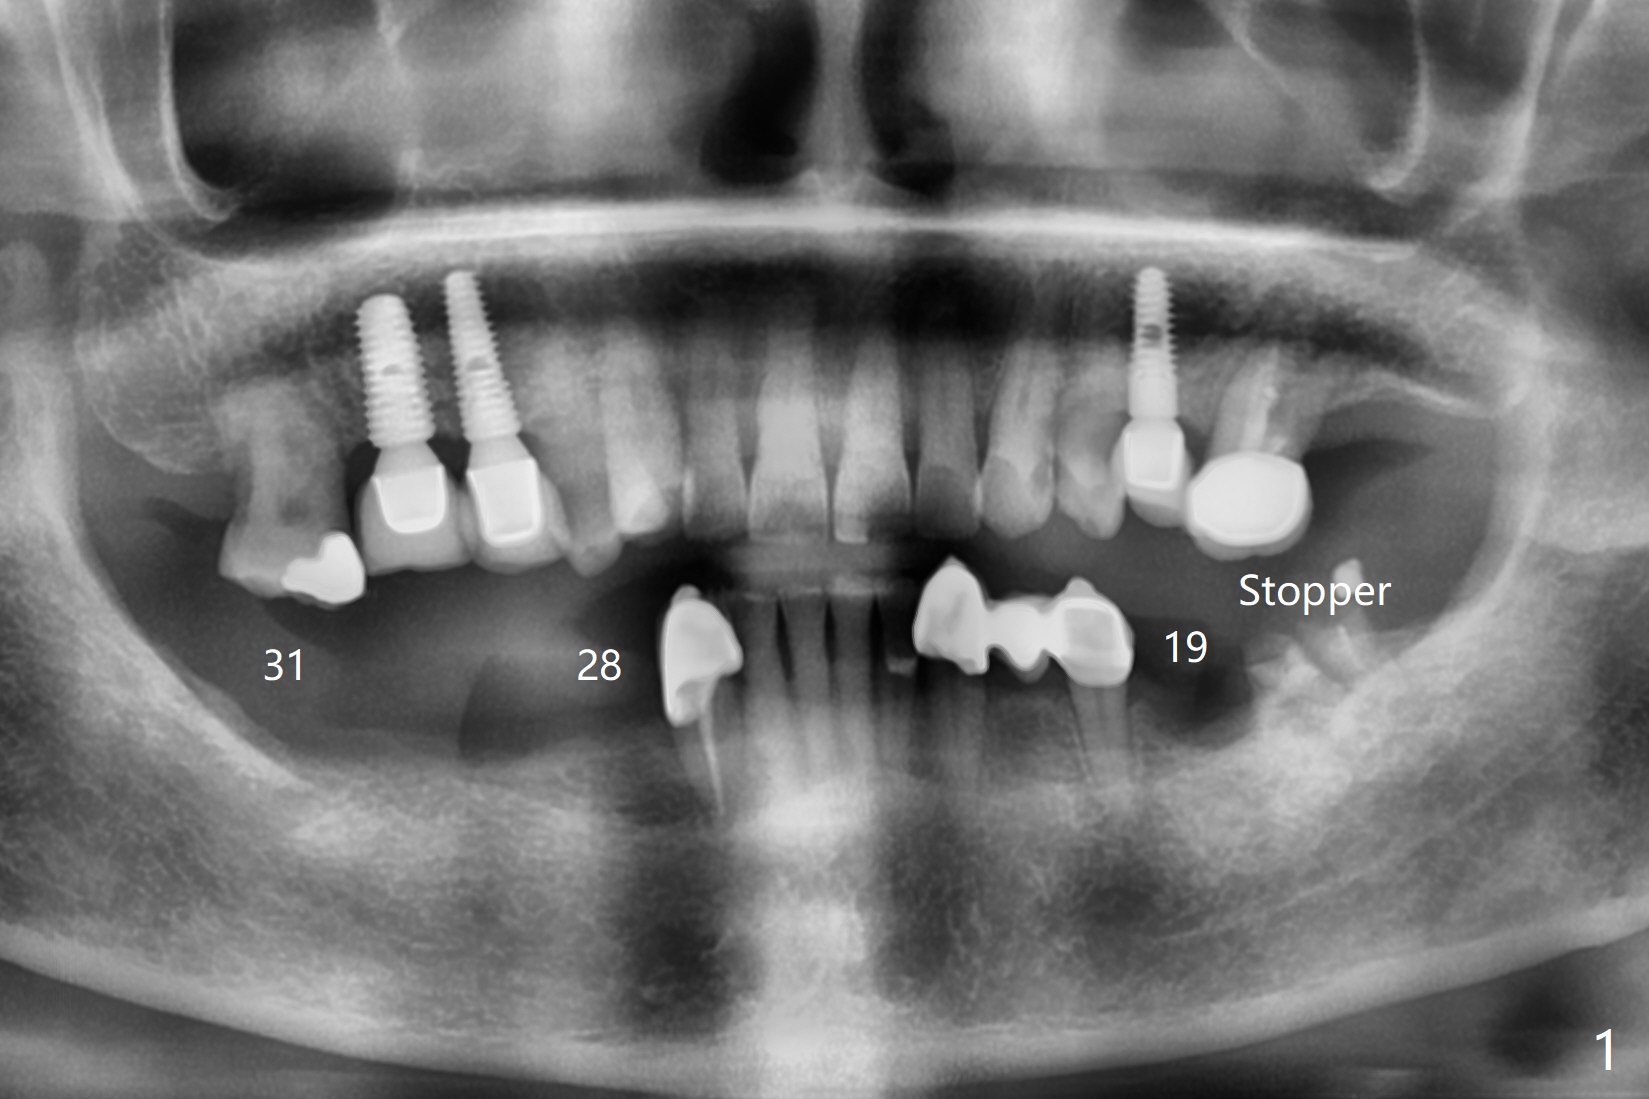

A 69-year-old woman requests conversion of the lower RPD to implant restoration. Initially implants are going to be placed at #19, 28, 29, and 31 (Fig.1,2). CT exam shows short bone at #31 (Fig.2). Please try to place implants at #28-30 for a cantilever FPD (Fig.3) if reasonable. When making guide(s), please use #18 residual roots as a distal stopper (Fig.1) if practical.